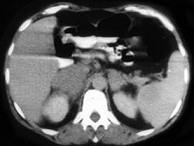

问题 男,65岁,腋下触及肿大包块,全身浅表淋巴结肿大,请结合所提供图像,选择最佳答案 ( )

选项 A、双侧肾上腺转移瘤 B、肾上腺癌 C、双侧肾上腺增生 D、双侧肾上腺淋巴瘤 E、双侧肾上腺腺瘤

答案 D